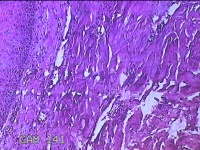

右侧食指远端结节

性别

男

年龄

47岁

临床诊断

皮下结节

一般病史

发现右侧食指3天。

标本名称

大体所见

灰白暗红色带皮肤样结节1.2x0.7x0.3cm一个,表面糜烂,切面灰白粉红色,质中。

应该是个良性病变,建议把主要病变区域来个地倍高倍,现在拍的炎症、溃疡的地方比较多